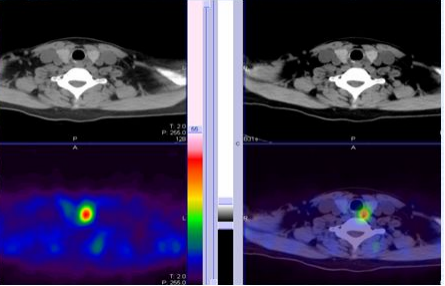

继发性甲状旁腺功能亢进时,通常四个腺体均增大而显影(图4)。甲状旁腺显像对于继发性或三发性甲状旁腺功能亢进患者的甲状旁腺定位敏感性仅能达到40%~90%。

图4 肾功能异常患者的继发性甲状旁腺功能亢进

甲状旁腺的SPCET/CT融合显像(即核素 MIBI 显像与 CT 显像的融合)是代谢的和解剖的影像结合,能够对继发性甲状旁腺功能亢进症(SPTH)患者的甲状旁腺结节进行手术前精确定位。SPECT可提高甲状旁腺亢进结节检出的敏感度并能提供更精确的定位,SPECT/CT(图5):它能提供解剖和功能的融合图像。

图5 甲状旁腺增生的SPECT/CT融合图像